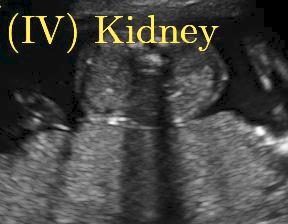

Fig. 6 compares the shadow confidence maps of the state-of-the-art methods and the proposed methods. RW and have the same parameters as used for Table I. The shadow confidence maps of the baseline, the proposed method and the proposedAG method are generated directly from input shadow images by confidence estimation networks. Overall, the proposed method and the proposedAG method achieve more visually reasonable shadow confidence estimation than the baseline and the state-of-the-art on different anatomical structures shown in Fig. 6. The proposed method and the proposedAG method are able to highlight multiple shadow regions while the RW algorithm shows limitations for most cases, especially for disjoint shadow regions.

Row I in Fig. 6 shows a fetal brain image from . The confidence estimation of shadow regions from the baseline, the proposed method and the proposedAG method are similarly accurate since we use fetal brain images to train the confidence estimation networks in these three methods. These outperform [16] and [22]. Rows (II-IV) in Fig. 6 show shadow confidence maps of non-brain anatomy from , including lips, abdominal and cardiac. The baseline failed on unseen data during inference. However, the proposed methods are able to generate accurate shadow confidence maps because of the generalized shadow features obtained by the shadow-seg module. Furthermore, the “Lips” example shows that our method is capable of detecting weaker shadow regions that have not been annotated in manual segmentation. This indicates that the confidence estimation network has learned general properties of shadow regions.

-D Alternative Examples of Shadow Confidence Estimation

We show an alternative group of examples for the confidence estimation of shadow regions (shown in Fig. 14). These examples include fetal brain from , and cardiac, lips, kidney from . Similar to the Fig. 6 in the main paper, Fig. 14 shows that the baseline fails to handle unseen data while the proposed method and the proposedAG method are able to predict pixel-wise confidence of multiple shadow regions. These examples demonstrate that the shadow-seg module is able to generalize the shadow representation and transfer shadow representation from the shadow/shadow-free classification task to a confidence estimation task.